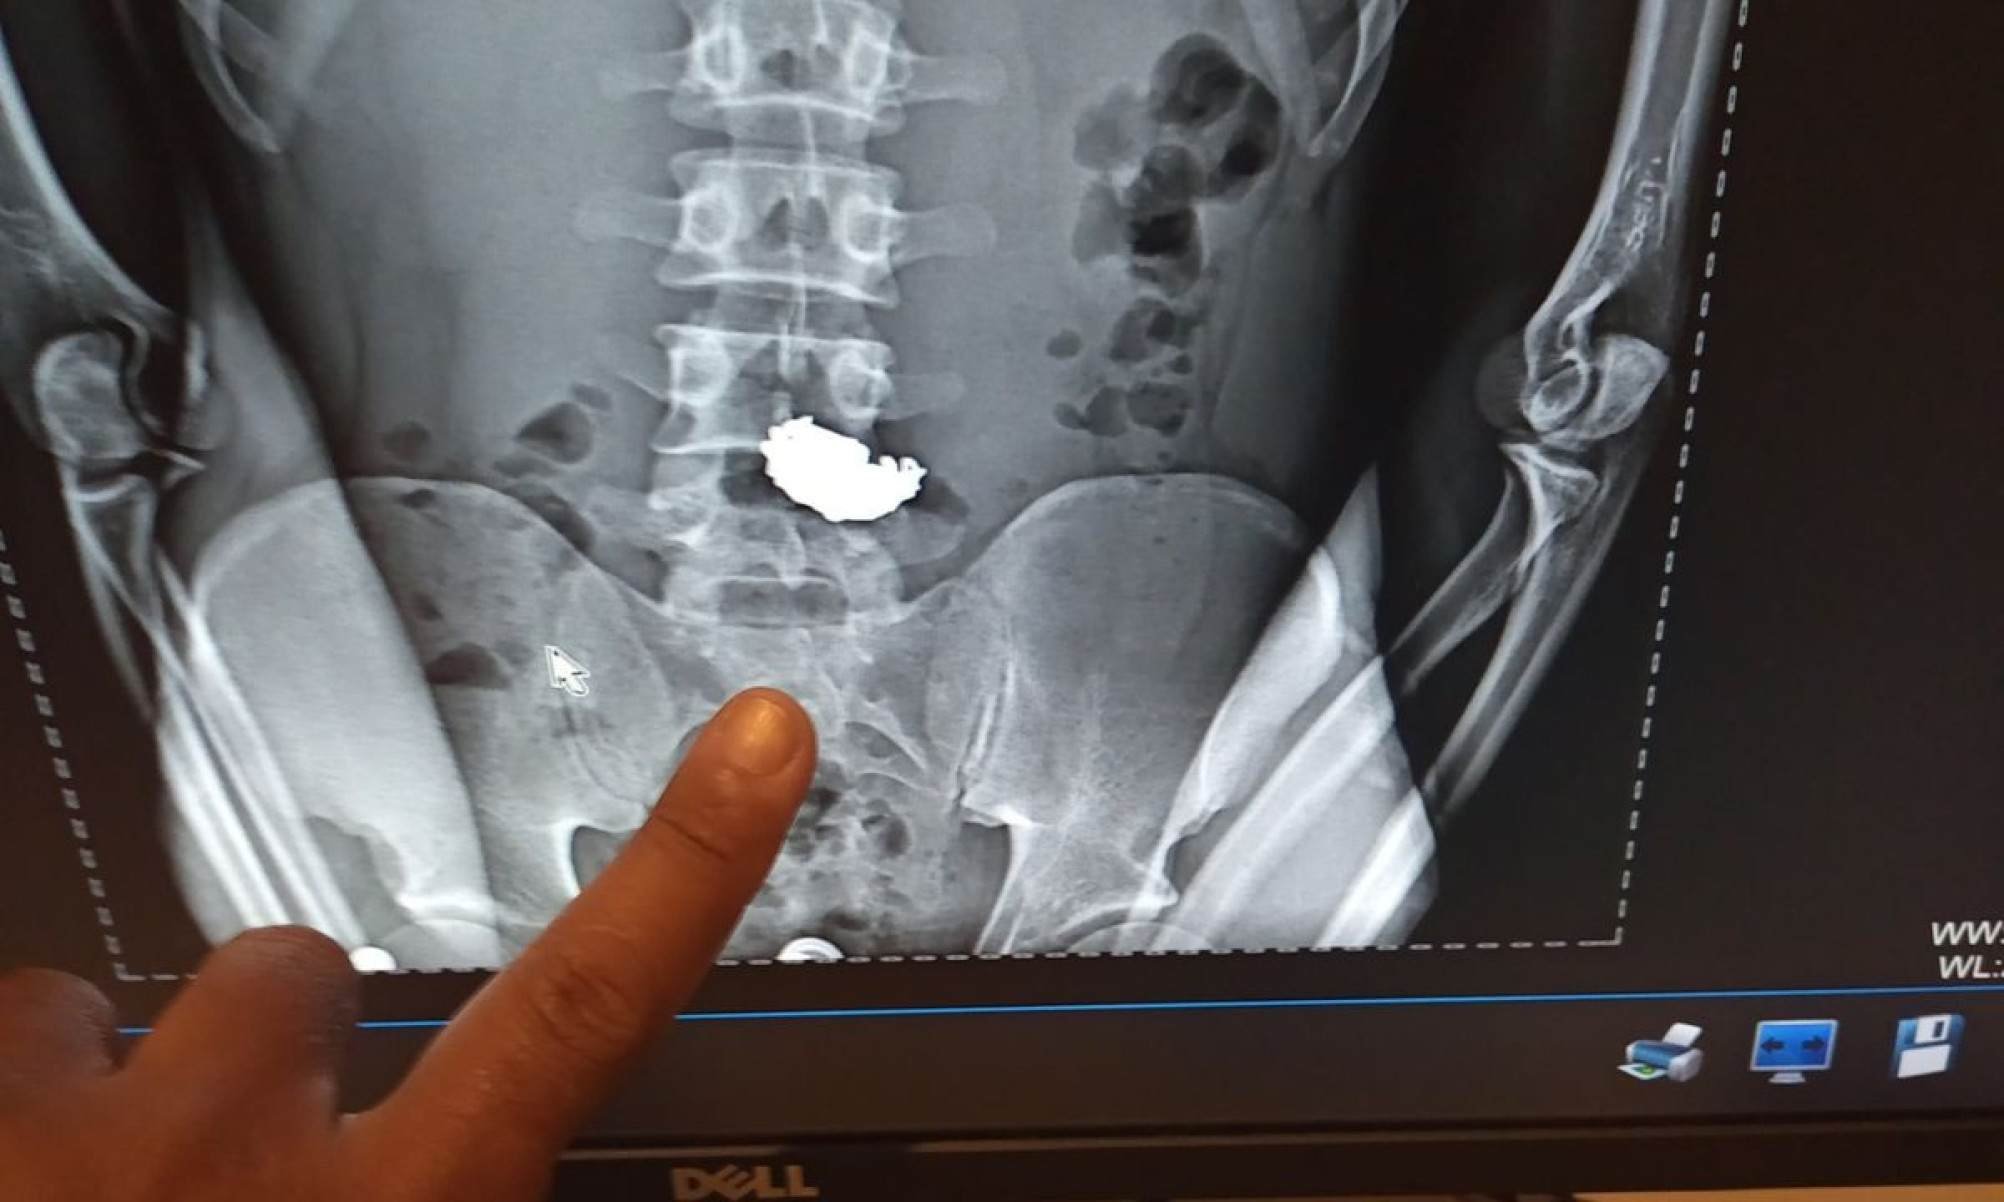

Um homem foi preso depois de furtar uma correntinha de ouro na Feira Hippie, na Avenida Afonso Pena, no Centro de Belo Horizonte (MG), na manhã desse domingo (29/6). Ele engoliu o colar e o objeto foi encontrado em seu corpo graças a um raio-X.

Conforme os registros, ele foi encaminhado ao Hospital Odilon Behrens, no Nordeste da cidade. O jovem foi submetido a um exame de raio-x, que confirmou a presença do ouro no estômago.